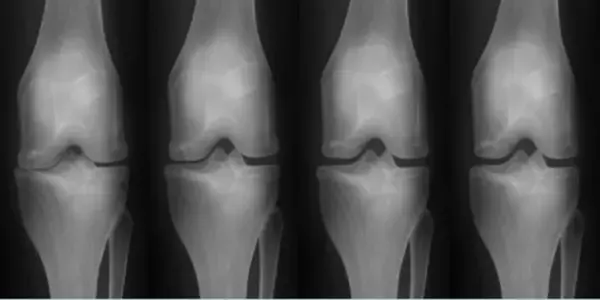

関節リウマチ(図1)や肝硬変(図2)など、特定の年齢層に限定されず、免疫力の低下で発生する可能性がある重症疾患の治療薬もやはりEHL BIOの核心研究分野です。

(図1)幹細胞施術前後の関節のレントゲン

両方の疾患ともに、既存の治療方式は「進行速度を遅らせること」に焦点を当てていましたが、EHL BIOが研究中の幹細胞治療剤の場合、患者本人の幹細胞の利用で免疫系拒絶反応を減らし「根本的な治療」が期待されます。

脂肪幹細胞は何度培養しても遺伝子の変異がなく分化能力に優れているため、様々な自己免疫疾患の治療に利用されており、関節リウマチの炎症反応を抑制するのに効果的です。また、肝硬化幹細胞治療プログラムは、他人の幹細胞ではなく自分の脂肪幹細胞を使用するため、細胞拒絶反応や副作用がなく、安全に肝細胞を回復できる治療方法であり、一度の脂肪採取で十分な量の幹細胞を抽出して何度も治療できるという利点があります。